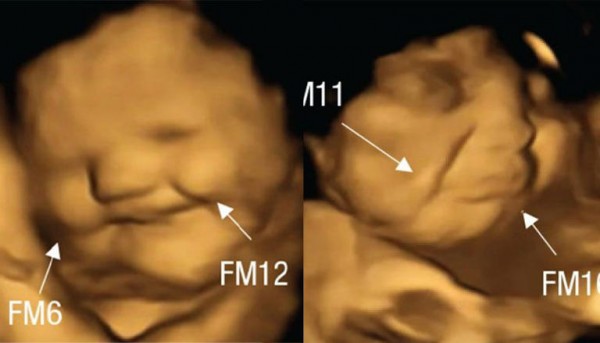

임산부가 먹는 음식에 따라 뱃속의 아기의 표정이 달라진다는 연구 결과가 나왔다.

22일(현지 시각) CNN 등에 따르면 최근 영국 더럼대학 등 공동연구진은 임신 32~36주차 사이의 18~40세 임신부 100명을 대상으로 태아가 자궁에서 맛과 냄새를 느낄 수 있는지에 대한 연구를 진행했다.

연구진은 임신부 35명은 유기 케일 캡슐을, 다른 35명은 당근 캡슐을 섭취하도록 했다. 당근은 성인에게도 단맛으로 느껴지고, 케일은 유아에게 시금치, 브로콜리, 아스파라거스 등 다른 녹색 채소 보다 더 쓰게 느껴지기 때문에 선택됐다고 한다. 나머지 30명은 어느 맛에도 노출되지 않도록 했다.

섭취 후 20분이 지나자 태아의 표정에 변화가 생겼다. 당근을 섭취한 집단의 태아들에게선 미소를 짓는 것처럼 올라간 입꼬리가 관찰됐다. 반면 케일을 섭취한 집단의 태아들은 입꼬리를 아래로 내리거나 입술을 꾹 다무는 등의 울상에 가까운 표정을 지었다.

영국 더럼 대학교 태아 및 신생아 연구소의 대학원 수석 연구원인 베이자 유스턴은 “이번 연구는 임신 중 태아의 맛에 대한 반응을 직접적으로 보여주는 첫 연구”라고 설명했다.